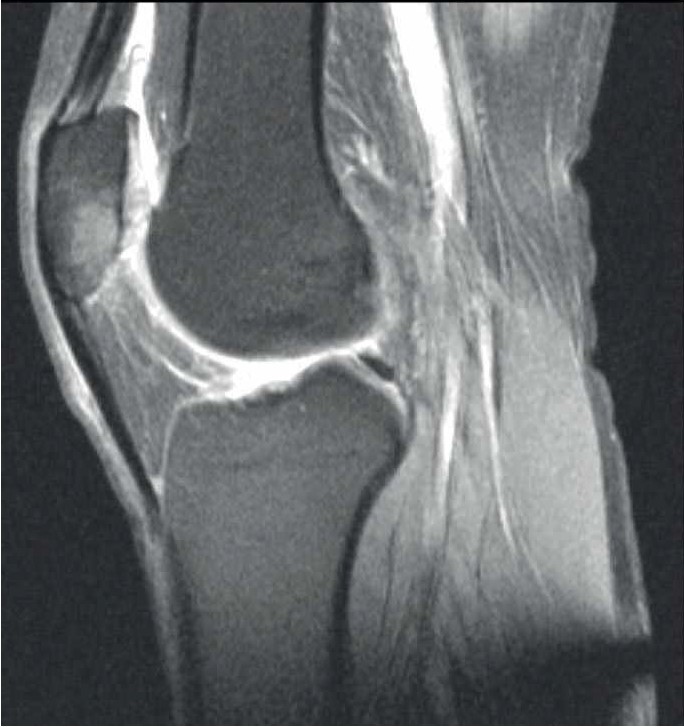

Лечилась у невролога консервативно с мая по сентябрь 2021 г. без положительной клинической динамики, а с сентября по декабрь 2021 г. – у травматолога по месту жительства по поводу тендопатии. Положительной клинической динамики не было. В марте 2022 г. на приеме у ортопеда выполнена МРТ правой стопы, диагноз – асептический некроз тела пяточной кости (рис. 4А).

Рис. 4. МРТ правой стопы у пациентки Г.

В марте 2022 г. произведена транскутанная остеоперфорация тела правой пяточной кости. Назначен терипаратид 20 мкг подкожно 1 раз в сутки. МРТ-контроль через 1 мес. На контрольном осмотре: пациентка отмечает восстановление функции правой нижней конечности, отсутствие болевого синдрома в правой пяточной кости (0 баллов по ВАШ). По данным контрольной МРТ – положительная динамика, отсутствуют признаки асептического некроза (см. рис. 4Б).

А – асептический некроз тела пяточной кости; Б – отсутствие признаков асептического некроза.